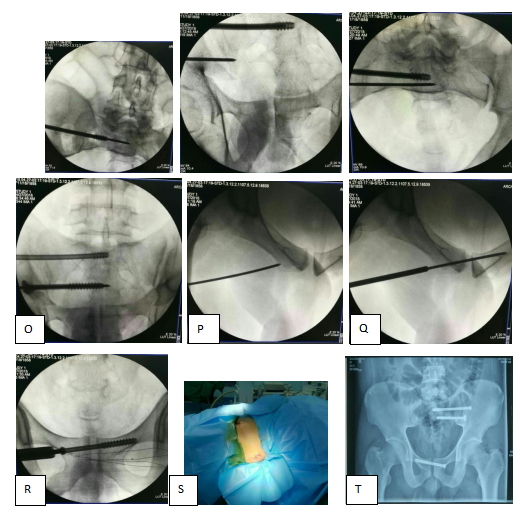

图:I、J、K、L、M、N、O、P、Q、R术中操作透视

图:S手术切口外观

图:T术后X光片